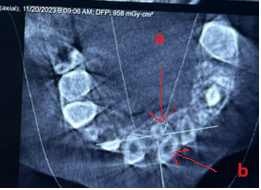

Răng thừa (b) mọc trong vòm miệng khiến cho R22 (a) mọc lệch xoay trục XQ răng toàn cảnh không thấy răng thừa do R21 (a) che khuất,(b) là R22 bị xoay trục

Hình ảnh răng thừa (a) xuất hiện rất rõ trên CT Cone Beam, (b) là hình ảnh R21

Hình 3: Tính ưu việt của CT Cone Beam trong chẩn đoán răng thừa

(Nguồn: Bệnh viện Đa khoa Tỉnh Quảng Trị)